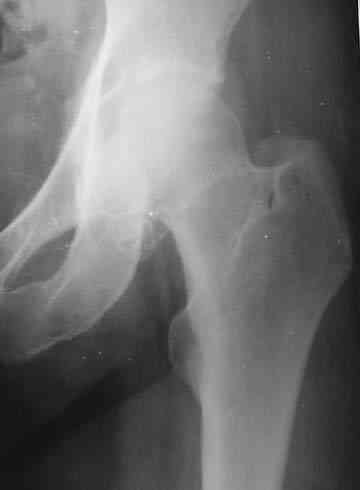

нормы. Рентгенологическое исследование. В прямой и боковой

проекции левого тазобедренного сустава отмечается уплотнение крыши

вертлужной впадины. В мягких тканях определяются округлой формы участки

неравномерного обызвествления.

Заключение. ДОА тазобедренного сустава. Хондроматоз слева в мягких тканях.